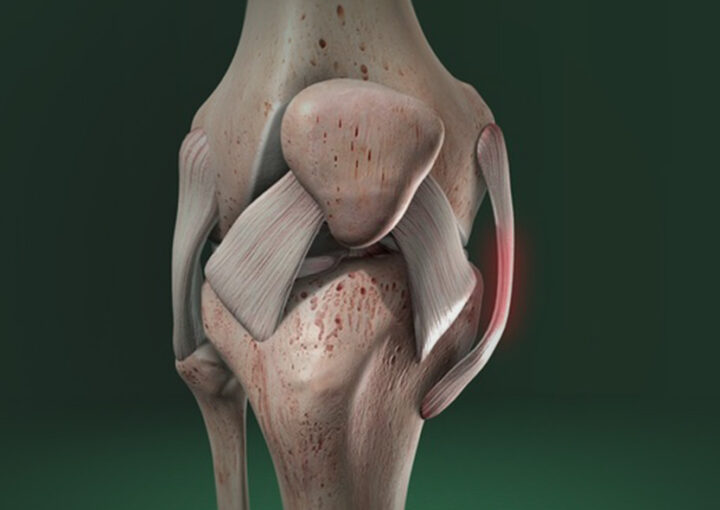

Dr. João Hollanda é médico ortopedista especialista em cirurgia do joelho com mais de 1.500 cirurgias de reconstrução do Ligamento Cruzado Anterior ao longo dos últimos 15 anos, incluindo atletas olímpicos de diferentes modalidades, atletas da Seleção Brasileira de Futebol e muitos “boleiros de fim de semana”.